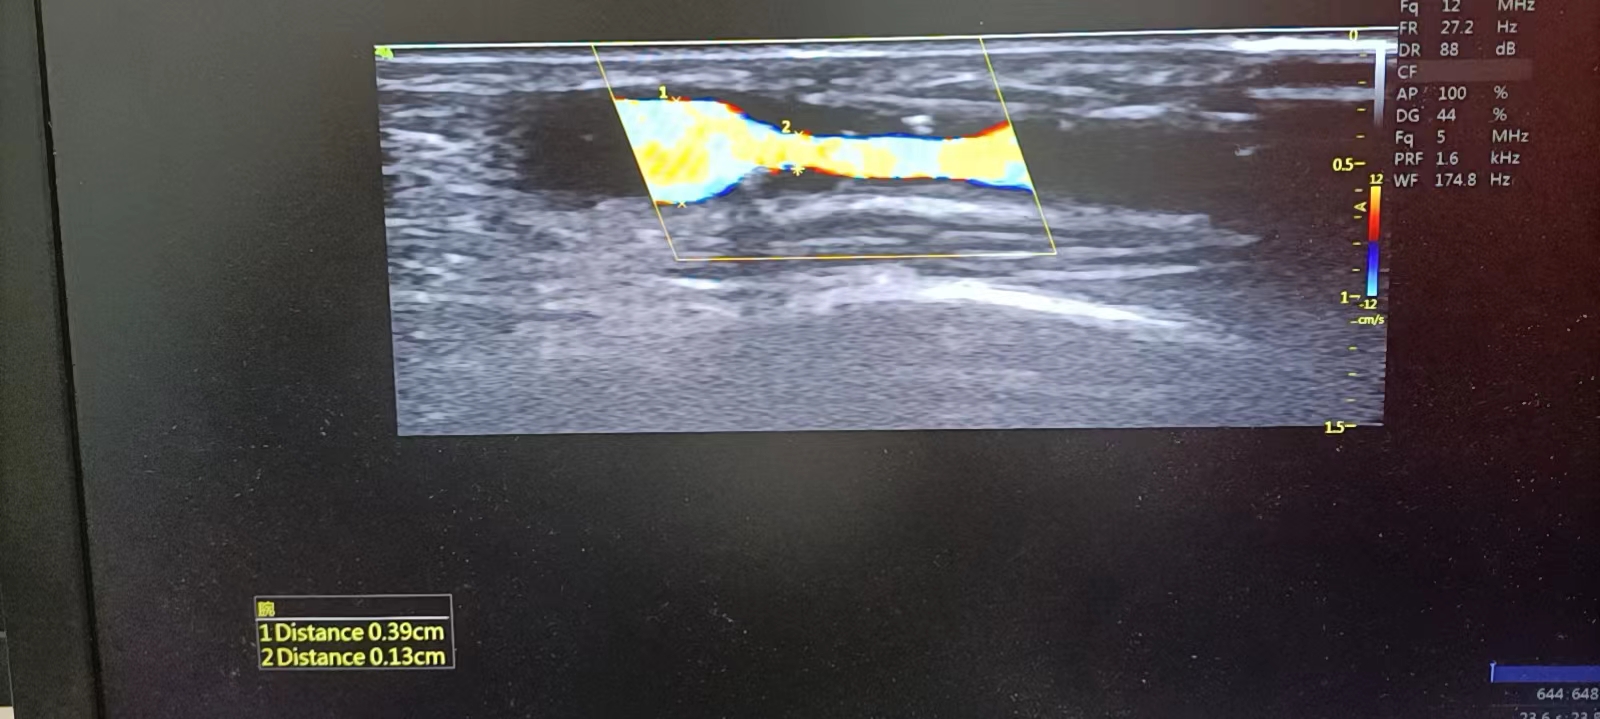

“B超引导下动静脉内瘘球囊扩张术(PTA)”

10月15日,维多利亚线路检测中心肾内科首次成功开展了“B超引导下动静脉内瘘球囊扩张术(PTA)”。经过前期各方面的充分准备,特邀浙一医院肾内科专家杨浩主任来院授课及会诊,为部分血液透析患者在B超下评估血透通路,以及指导在B超引导下行动静脉内瘘球囊扩张手术(PTA)。

中医院肾内科副主任雷红英和主治医师赖必亮在杨浩主任指导下,首次成功为5位患者实施此手术,术程顺利,术后患者内瘘震颤及血管杂音、管腔充盈度、透析血流量等情况明显改善,“生命通道”成功扩张,为患者继续血液透析给予保障,切实减轻了患者的身心痛苦和经济负担,让患者在家门口的医院就享受到省级医院同质化的医疗服务,得到患者一致好评。

介入球囊扩张治疗透析患者动静脉内瘘血管狭窄作为一项新技术,近年来逐渐得到推广应用。它是在影像引导下经皮穿刺血管,送入球囊扩张导管,对血管的狭窄部分进行扩张,恢复正常血管腔内径,使得原有珍贵内瘘血管资源得以继续保留。